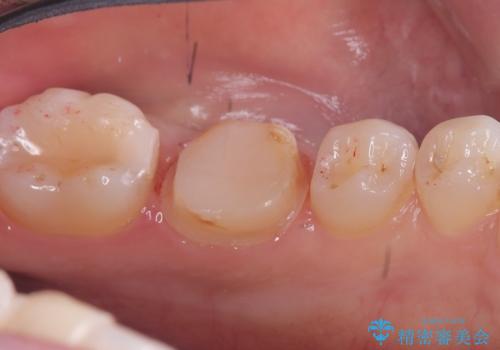

- 主訴:強く噛んだら歯がポロポロ欠けてきた。

左下6番目の歯の咬合面にプラスチックの材料が詰まっており、歯質がドーナツ状にしか残っていなかったため、歯質幅が比較的薄かった場所が欠けてしまったようでした。

今後の破折リスクを説明し、セラミッククラウンでのやり替えとなりました。

頬舌的レジンインレーが入っており、歯質幅の薄かった且つ強く咬合していた遠心側歯質が欠けてしまっていました。また新しい窩洞のインレーを入れても、近心側歯質の破折のリスクは抱えたままになることから、クラウンでの修復をおすすめし審美性・適合性のよいセラミッククラウンでのやり替えとなりました。